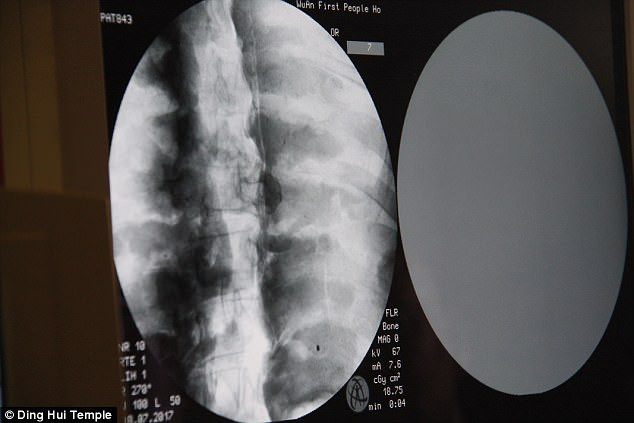

Các chuyên gia tiến hành chụp cắt lớp vi tính xác ướp đại sư Từ Hiền trước sự chứng kiến của các nhà sư, phật tử và phương tiện truyền thông.

Những người có mặt tại sự kiện trên đều vô cùng bất ngờ khi các chuyên gia thông báo thi hài đại sư Từ Hiền vẫn còn đầy đủ xương và sọ não hoàn chỉnh.

"Chúng ta có thể trông thấy xương cốt đại sư vẫn còn chắc khỏe như xương của người thường", bác sĩ Wu Yongqing chia sẻ.

Theo bác sĩ Wu Yongqing, xương hàm trên, hàm dưới, xương sườn, cột sống và tất cả khớp đều hoàn chỉnh. Điều này thật đáng kinh ngạc.